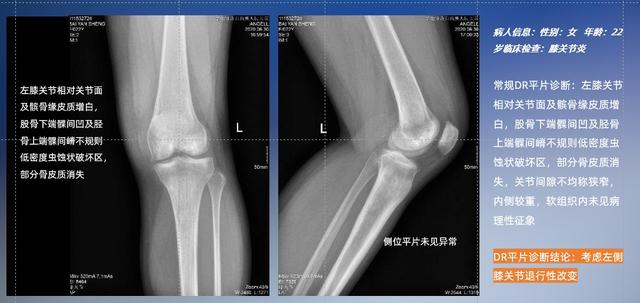

以膝關(guān)節(jié)疾病檢查為例,膝關(guān)節(jié)在解剖學(xué)意義上是一種較為復(fù)雜的最大關(guān)節(jié),由脛骨上端、股骨下端及髕骨組成。在股骨與脛骨的關(guān)節(jié)面之間存在兩塊半月板,分別處于內(nèi)側(cè)、外側(cè)。膝關(guān)節(jié)的運(yùn)動(dòng)主要為伸、屈,在半屈位時(shí)可進(jìn)行小幅度的旋外、旋內(nèi)運(yùn)動(dòng)。隨著現(xiàn)代人們體育生活以及肥胖的增加,膝關(guān)節(jié)疾病出現(xiàn)高發(fā)趨勢(shì),特別是關(guān)節(jié)磨損、膝關(guān)節(jié)炎與骨關(guān)節(jié)炎等關(guān)節(jié)退行性改變,長時(shí)間的內(nèi)翻負(fù)荷會(huì)造成內(nèi)側(cè)關(guān)節(jié)軟骨、骨性關(guān)節(jié)面的磨損。目前針對(duì)此類疾病的檢查主要為平片下的負(fù)重位檢查、CT檢查以及MRI檢查,相較于非負(fù)重位檢查,負(fù)重位檢查能更加真實(shí)反映膝關(guān)節(jié)結(jié)構(gòu)中脛骨、股骨、髕骨實(shí)際對(duì)位關(guān)系和關(guān)節(jié)面的形態(tài)特征及關(guān)節(jié)間隙大小,對(duì)膝關(guān)節(jié)骨關(guān)節(jié)病診斷準(zhǔn)確率高。

普通平片掃描與WR-3D掃描前后診斷結(jié)果對(duì)比

在負(fù)重位狀態(tài)下,數(shù)字化X線三維掃描與重建,能夠更好的呈現(xiàn)受檢者關(guān)節(jié)受力改變的狀態(tài)。安健科技創(chuàng)新的WR-3D動(dòng)態(tài)三維影像重建系統(tǒng),通過數(shù)字化X線攝影完成三維掃描并重建三維影像信息,包括斷層圖像重建、MPR多平面重建、MIP重建以及VR體繪制。其掃描時(shí)間短,劑量相較于CT設(shè)備大幅縮減,同時(shí)成本更低,在臨床診斷以及醫(yī)療方案制定中具有極大的價(jià)值意義。而相較于普通平片下的負(fù)重位掃描,負(fù)重位動(dòng)態(tài)三維影像重建技術(shù)能夠避免二維狀態(tài)下的組織結(jié)構(gòu)重疊、密度分辨率不足、組織解剖結(jié)構(gòu)難以分辨等問題。WR-3D支持多角度的三維觀察,能全面的呈現(xiàn)被檢查部位在多個(gè)角度下的三維影像信息,極大的降低了二維負(fù)重位檢查帶來的漏診率。